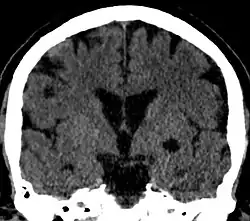

Choroidal fissure cyst

A choroidal fissure cyst is a cyst at the level of the choroidal fissure of the brain. They are usually asymptomatic and do not require treatment.